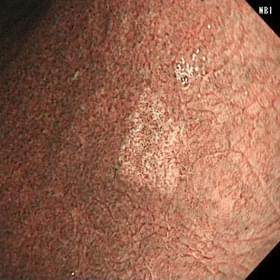

白色光通常観察の写真 NBI通常観察の写真 NBI拡大観察の写真

白色光通常観察 NBI通常観察 NBI拡大観察

(血管や粘膜の不整を認める)

早期胃癌(印環細胞癌)